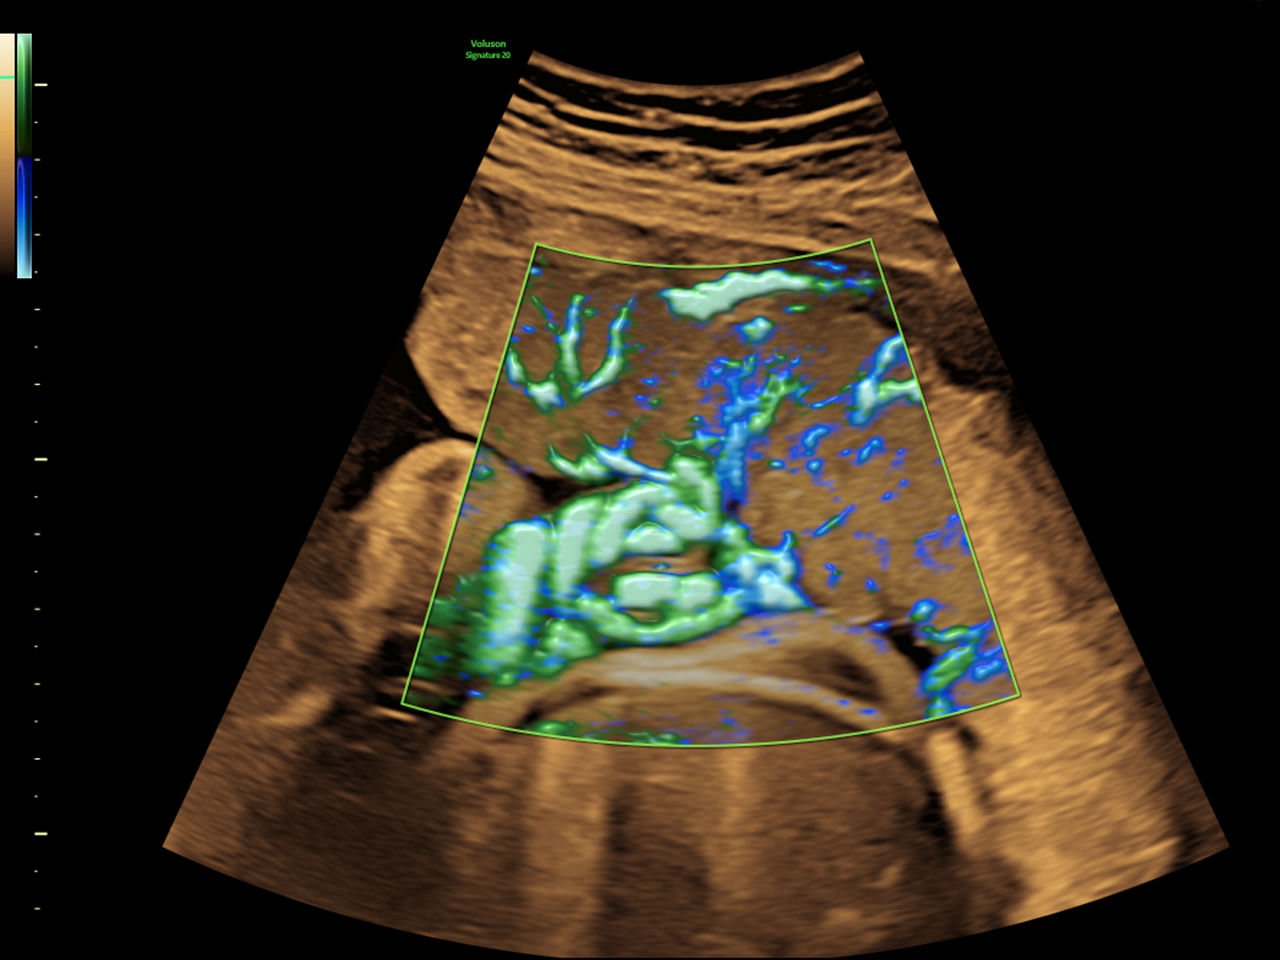

Fast, easy 3D-like blood flow visualization

Next level color Doppler that delivers exceptional sensitivity for easy, fast visualization of blood flow, displaying a 3D like appearance as seen in this 27-week fetal heart.